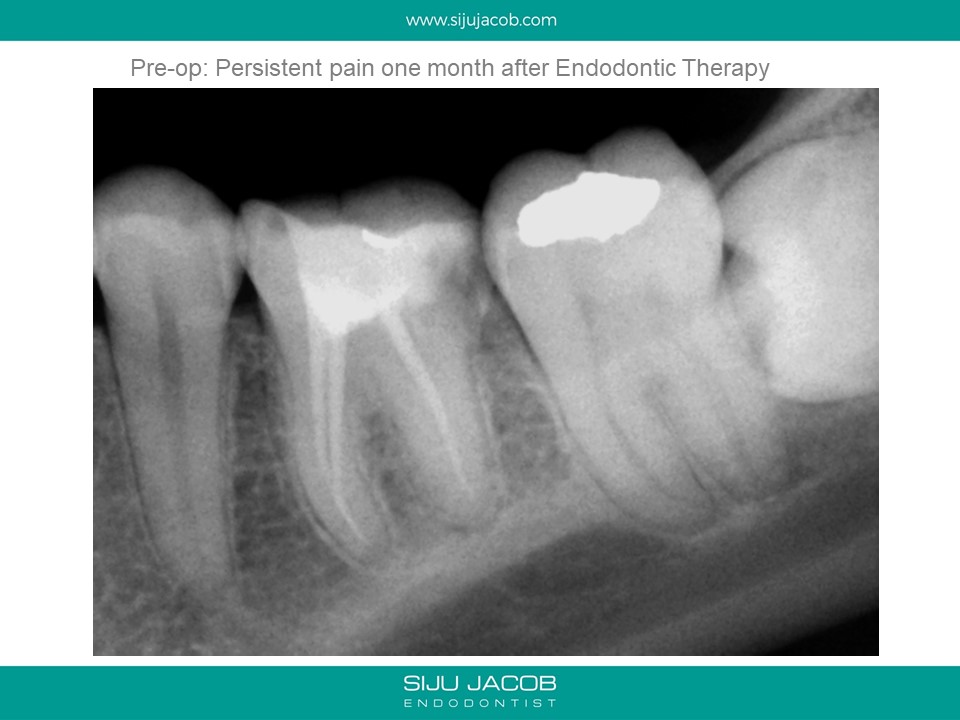

This patient had sensitivity to cold after an RCT on a lower molar. Sensitivity persisted even after a month. Re-treatment revealed a missed distal canal/root that was still vital and hyperaemic.